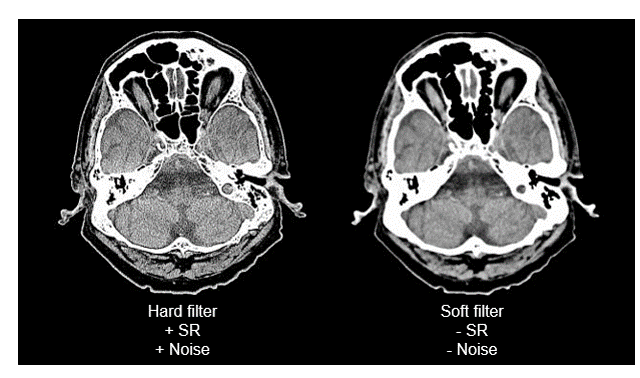

SR and Hard Filter

The harder the filter, the spatial resolution increases and the more the noise in the image increases.